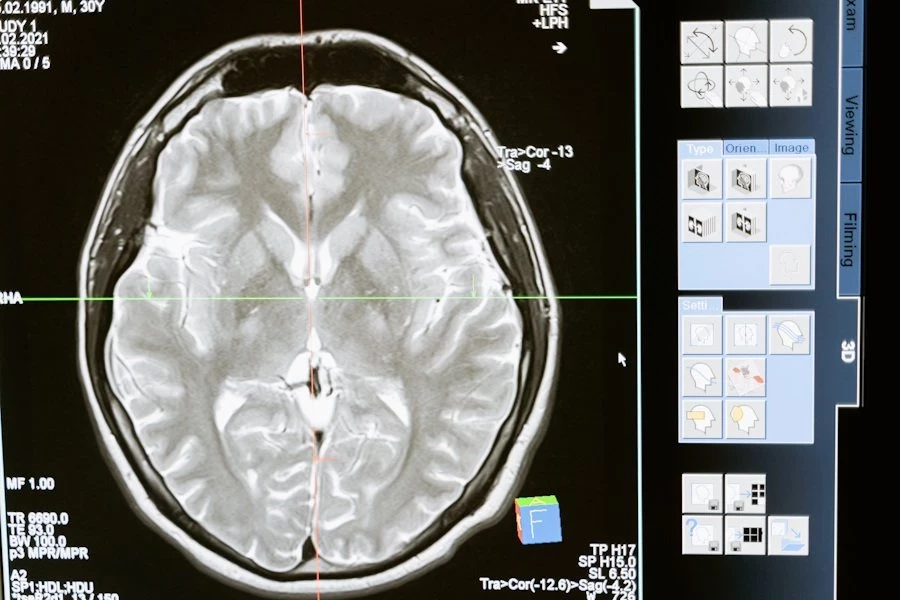

Проблемы с мозгом могут проявляться различными способами: от общих симптомов, таких как слабость и головные боли, до конкретных функциональных нарушений, таких как нарушения речи или координации движений. К примеру, недавно «Определены участки генома, связанные с ускоренным развитием деменции».

По данным неврологов, мозг чувствителен к воздействию различных факторов, включая алкоголь и курение, но наиболее вредными являются дефицит кислорода и глюкозы в крови. Нейроны в мозгу зависят от поступления глюкозы через кровь, и при отсутствии кровообращения они начинают умирать в течение пяти минут. Стресс также влияет на мозг, меняя химический баланс и передачу сигналов.